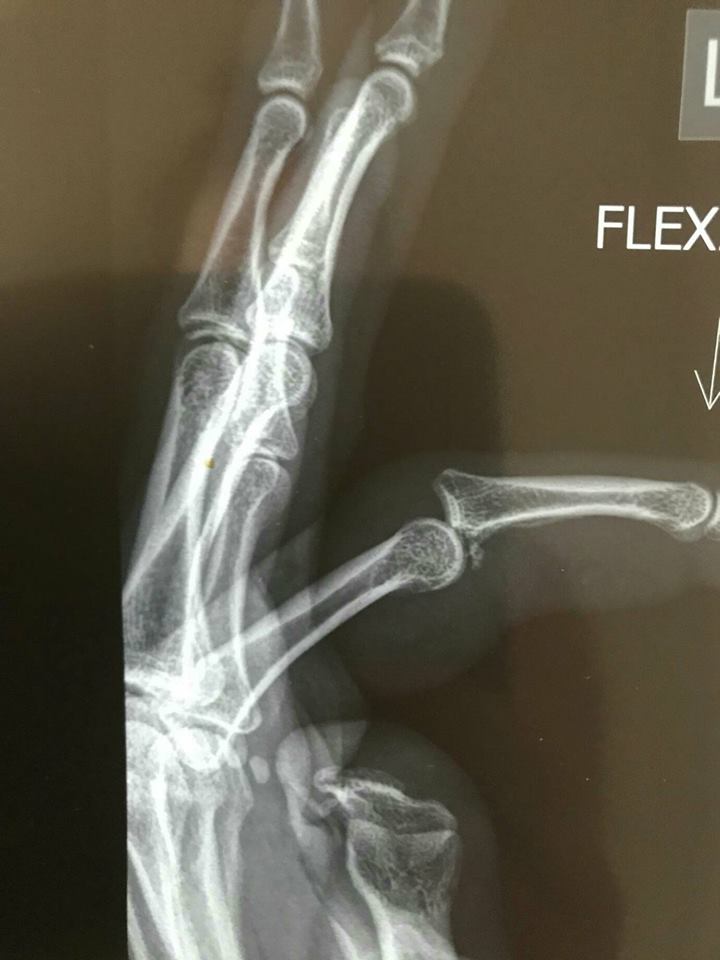

Lightning veteran Laura Hodges tomorrow goes in for surgery on her broken ring finger, an injury she suffered in the preseason - go here for more - but which she taped up and played with in Adelaide's first two games!

Check out the X-rays again. Whoa.

Yep. That's what you call a break.